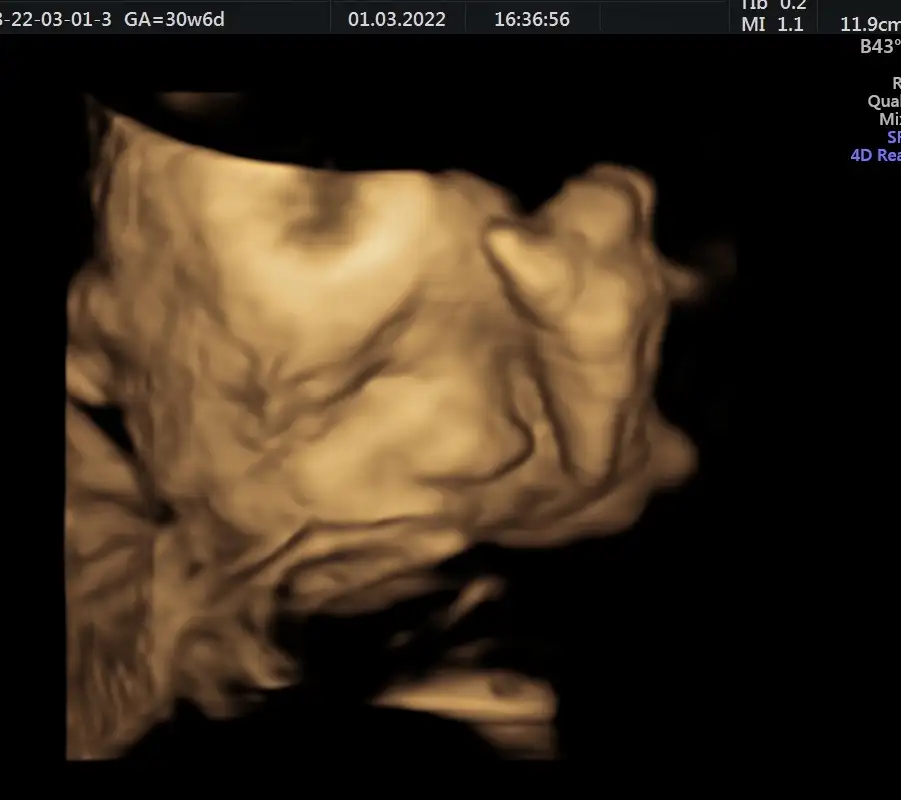

Her şey yolundaymış kızlar. Oğluşum 1800 gr, 43.87 cm olmuş